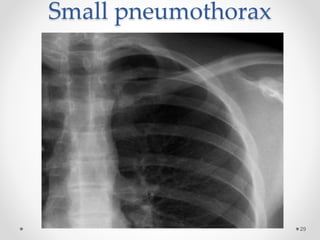

Plane chest X-ray film

Small pneumothorax